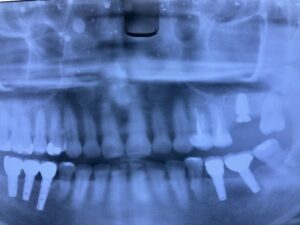

インプラントの上部構造の最終補綴物にメタルボンドと呼ばれるセラミックが使用されていました。今でも使用しますが1番の欠点として破折の可能性があることです。近年、物性や神秘性が格段に向上したジルコニアが、第一選択上がるようになりました。